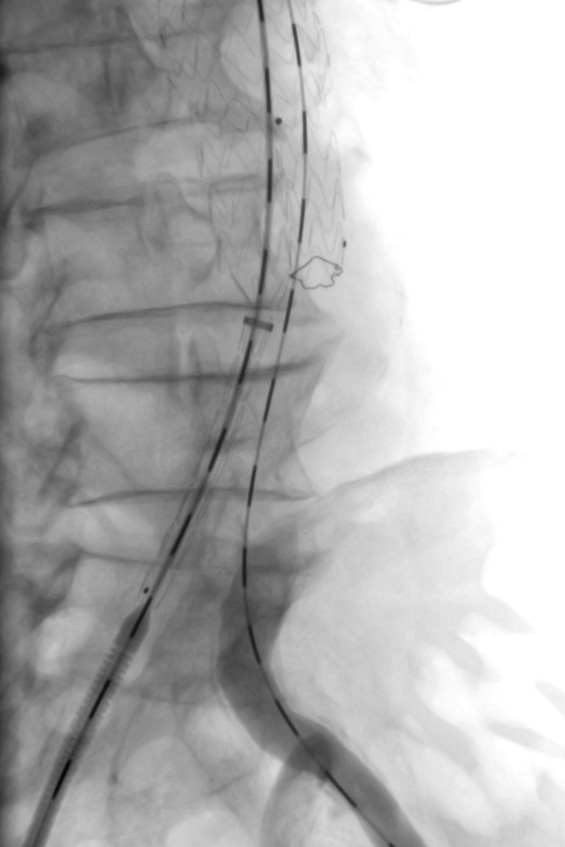

Symedrix has developed the WiTRAC® pre-shaped and scaled guide wire specifically designed to improve AAA procedures.

The AAA wire has three independent zones of stiffness providing optimal support. The ultra-stiff proximal portion of the wire facilitates easy advancing of introducer sheath. The super-stiff distal portion adapts perfectly to the anatomy in the abdominal aortic area and provides sufficient guidance and support for the AAA introducer system. The scaling provides additional support during endovascular procedures. The Tip allows atraumatic positioning in Aorta, thereby protecting the Vessels during the implantation of the stent grafts.

A PTFE-coated, stainless steel wire is the key to providing maximum support and low surface friction during complex procedures.

The smooth transition from the stiff wire to the flexible tip facilitates atraumatic vessel navigation.